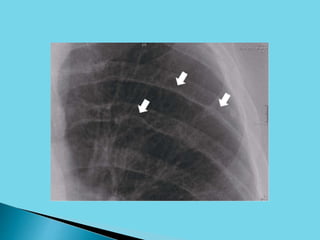

 Exuberant collateral circulation “around” the

coarctation often develops through markedly

enlarged intercostal and internal mammary

arteries; expansion of the flow through these

vessels can lead to radiographically visible

“notching” of the ribs.